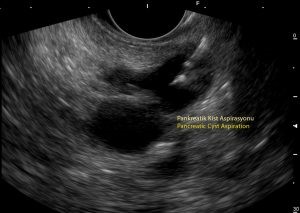

• Pankreas kistlerinin araştırılması ve örneklenmesi

-Kist sıvısı örneklemesi yapılan kişilerde işlemden sonra kist sıvısı içerisinde infeksiyon gelişmesi riski söz konusu olabilmektedir. Bu riski azaltmak için işlem öncesi antibiyotik tedavisi verilmekte ve yaklaşık 3-5 gün antibiyotik tedavisine devam edilmektedir. Ayrıca kist sıvısı tama yakın boşaltılarak infeksiyon riski azaltılmaktadır. Kistik olmayan alanlardan örnek alınmasında infeksiyon riski yok denecek düzeyde olduğu için bu gibi hastalarımızda antibiyotik verilmemektedir.